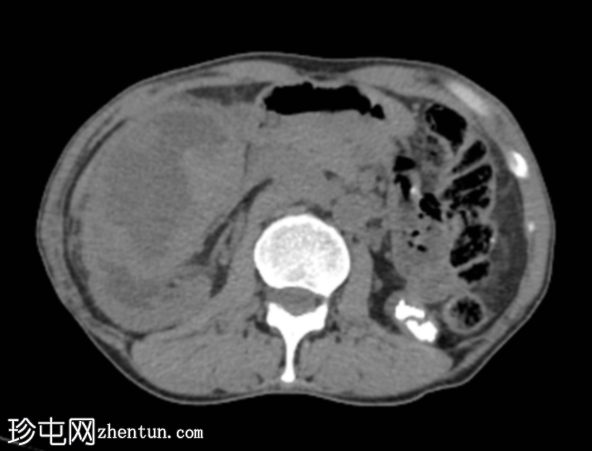

MRI

4.png

冠状位

T2加权像

再次观察到上述肾前部外生性病变,其实性成分在T1加权像上呈等高信号,在T2加权像上呈低信号,伴有碎片扩散受限和低ADC值(化脓性物质)。囊性成分内部可见液-碎片/脓液界面。可见内部低信号结石。可见肾周模糊影。该病变压迫并可能侵犯右肾盂,导致中度肾积水。

病灶不规则的低信号,以及液-液界面伴有碎屑(可能为化脓性物质)扩散受限和肾周模糊,再次高度提示炎症性病变(黄色肉芽肿性肾盂肾炎,XGP),而非可能性较小的肿瘤。

左肾萎缩,体积较小,内含多发低信号结石。